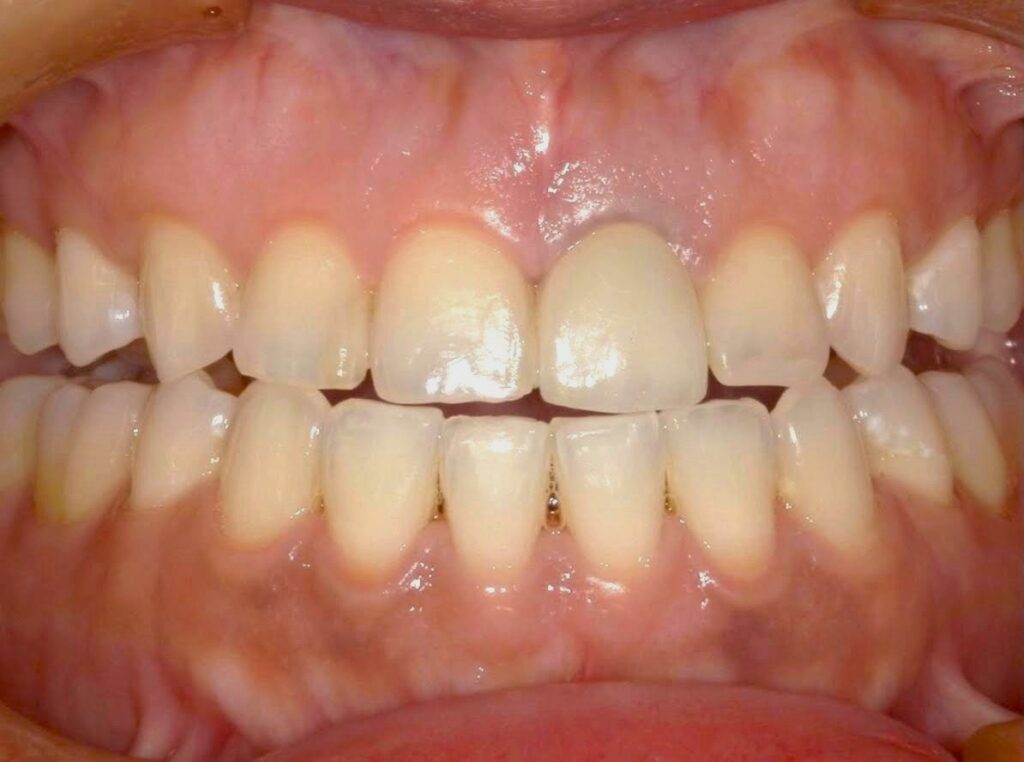

Before

After

年齢 | 30代前半 |

性別 | 女性 |

主訴 | 前歯の被せ物の色味が合っていないのでやり直したい |

施術内容 | 色があっていない保険適応のCAD/CAM冠を外して、自費補綴のジルコニアに被せなおしています。 |